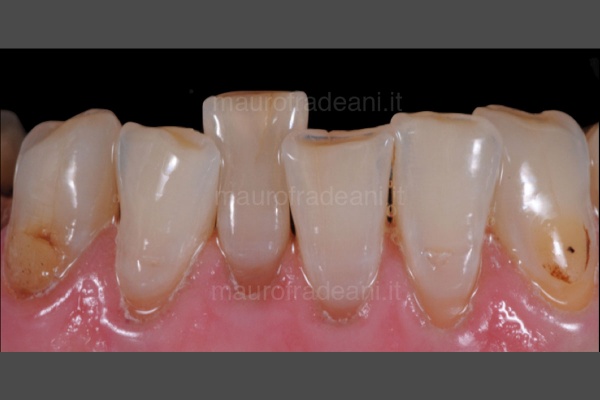

1/5: The patient presents severe dental crowding with misalignment of the lower incisors, dental shape and volume alteration with enamel wear of the gingival collars and worn incisal margins causing esthetic and functional issues. Before treating this case with prosthetic restorations, a preventive orthodontic realignment is necessary.